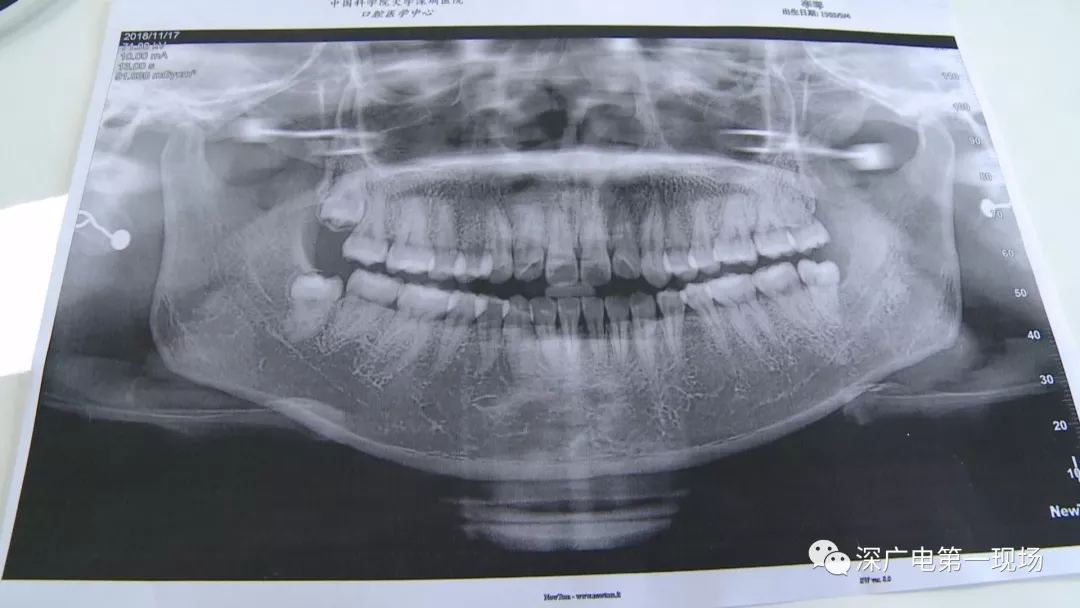

復雜牙拔出程序較復雜

針對李女士的情況,醫(yī)生介紹,當時要想拔出李女士的這顆智齒,難度還是很大的,屬于復雜智齒的拔除術(shù)。她的風險在于距離神經(jīng)管近,同時這顆牙齒完全埋在牙床最后的位置,直接往外拔,會加大頜骨的風險,因此需要先切開,讓牙齒暴露后,切小再慢慢地拔出。